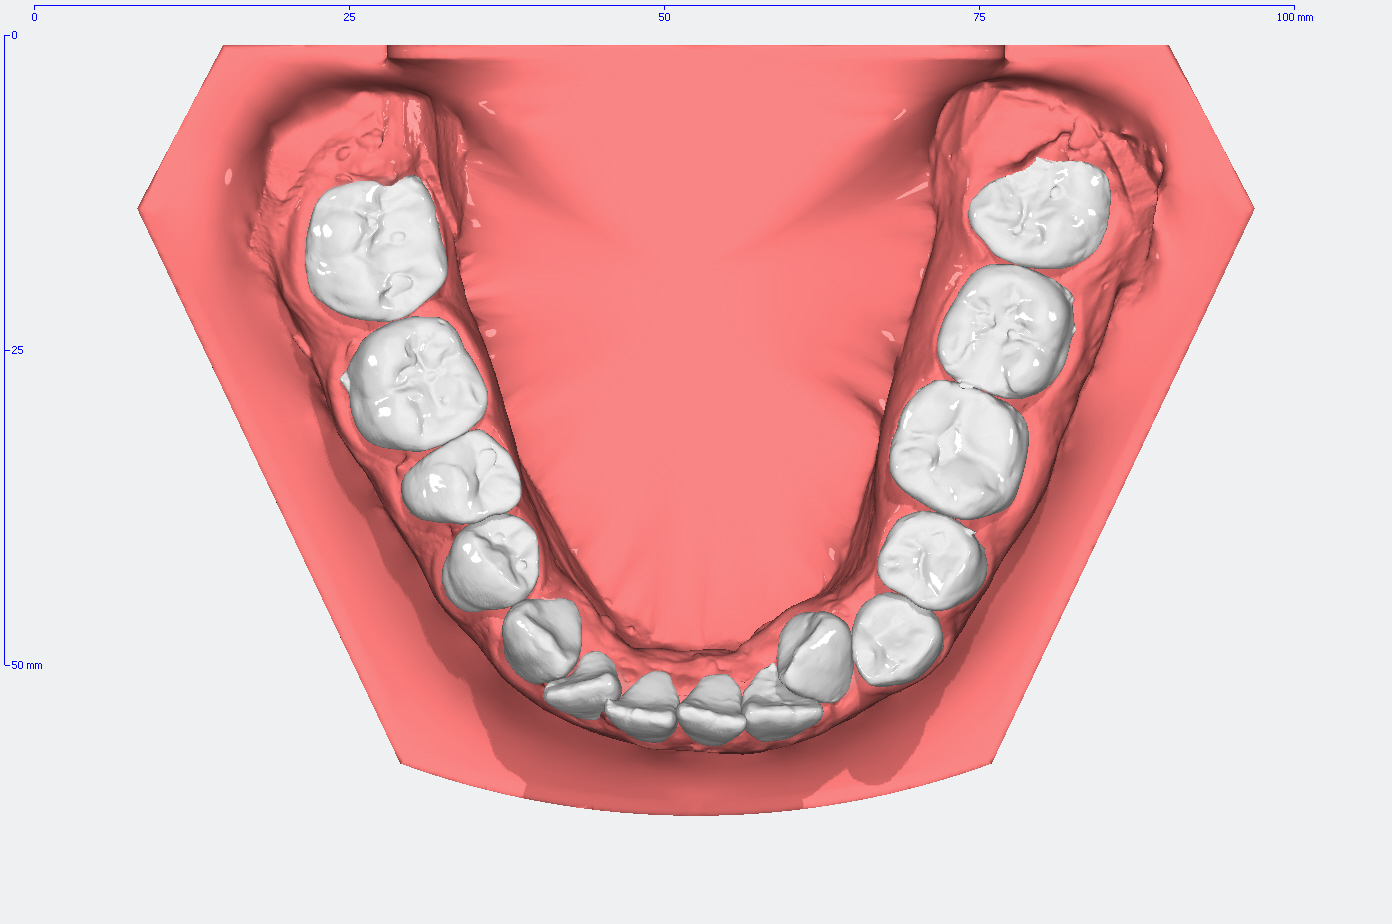

Die Entwicklung der Zahnstellung im Gebiß anhand von 3D Modellen

In den Abbildungen unten sehen Sie den Vergleich der Zahnstellung in den Gebissmodellen in der ursprünglichen Form und nach der kieferorthopädischen Behandlung.

Moderne Diagnostik mittles 3D-Modell Analyse

3D Intraoralscanner – einfacher, effektiver und angenehmer!

Anders als bei herkömmlichen Gebiss-Abformungen mit Alginat, können wir Ihre Zähne bei uns digital abformen. Dank digitalen Videotechnik scannen wir die Zähne und Ihre umliegenden Strukturen schnell, effizient und beinahe berührungsfrei.

Das System erstellt daraufhin ein dreidimensionales Abbild, das in Echtzeit auf dem Monitor betrachtet und analysiert werden kann.